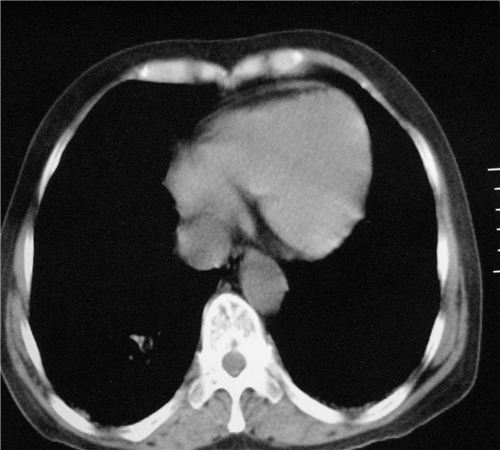

标题: CT26849:女67岁反复胸痛两天余,临床考虑夹层。 [打印本页]

标题: CT26849:女67岁反复胸痛两天余,临床考虑夹层。

右肺感染,未见夹层。

未见夹层

既然考虑夹层,建议强化!另:右下肺感染!

1)右肺感染性病变。2)建议行ct增强扫描或mri检查排除主动脉夹层。

双下肺感染,右侧显著。有无夹层,增强扫描后再诊断。

1. 感染性病变,2.未见夹层,3.食道未见异常。

平扫未见确切夹层征,建议必要时增强扫描或mri检查。